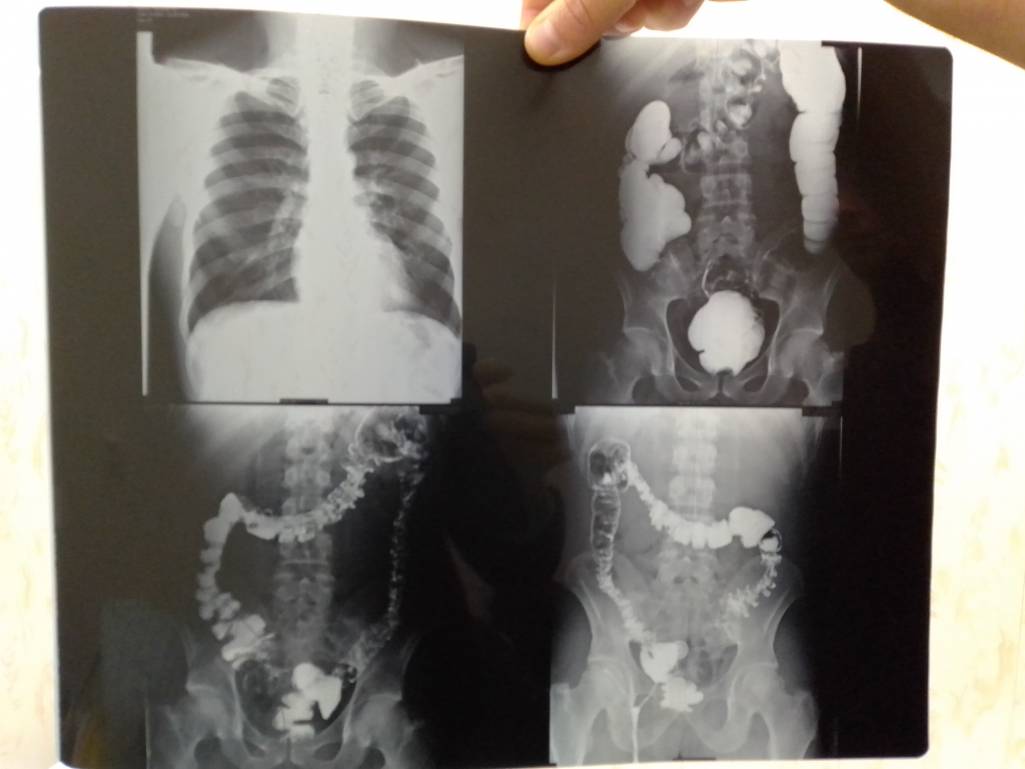

Деньги на лекарства - IMG_20200105_134627.jpg

Деньги на лекарства - IMG_20200105_134622.jpg

Деньги на лекарства - IMG_20200105_134550.jpg

Деньги на лекарства - IMG_20200105_134542.jpg

Деньги на лекарства - IMG_20200105_134444.jpg

Деньги на лекарства - IMG_20200105_134433.jpg